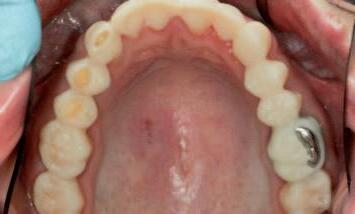

n Upon removal of the tooth reduction guide, a subtle, conservative but clinically meaningful elimination of anticipated interferences may be confirmed (Figure 5). The guided reduction procedure has simplified the subsequent process of tooth preparation for indirect restorations, at the next step of the treatment plan.

n Subsequent conventional tooth preparations can now be implemented as minimally as possible, as interferences have been eliminated with control and precision.

FIGURE 5: Evaluation of the clinical situation before and after the planned tooth reduction, highlighting the subtle and conservative but clinically meaningful changes that have been made, prior to tooth preparations for indirect restorations.